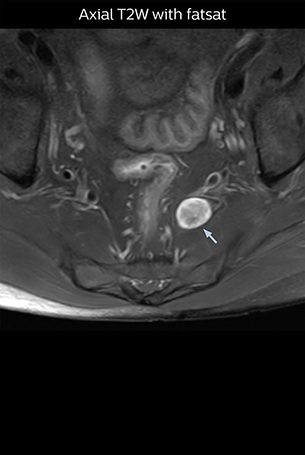

“Although symptoms of typical disc herniation and atypical hernia are very similar, the actual site of herniation is different. It is therefore important to characterize the nerve’s condition both inside and outside of the intervertebral foramina. “Conversely, if we see no abnormality in NerveVIEW, we can assume at least that there is no severe condition that requires surgery. Like this, it can help us avoid unnecessary surgery. NerveVIEW can have a tremendous impact in this way.”

“NerveVIEW is really useful for those cases where a nerve disorder is strongly suspected based on the clinical examination but our regular MRI images do not show any findings. These atypical herniations and spinal canal stenosis, occurring in 5% to 15% of the total lumbar herniation/stenosis cases are our main target when using NerveVIEW,” says Dr. Yabuki.

“The intra-luminal signal of veins, especially around the intervertebral space, can be suppressed well with NerveVIEW. As a result, we can easily observe the detailed nerve structure around the posterior ganglion,” he says. “This is why we use 3D NerveVIEW for intraforaminal stenosis and extraforaminal stenosis/herniation (lateral disc herniation). On the other hand, if herniation is suspected to exist inside the dorsal root ganglion (DRG), balanced TFE or ProSet-FFE is applied. NerveVIEW is not suitable for evaluating the median type of herniation.” The SE-EPI DWI-based method for MR neurography works well for large FOV exams like whole-body MRI, but focal examination of nerves is often limited by the attainable spatial resolution (both inplane and slice direction) and geometric distortion. “3D NerveVIEW achieves higher in-plane resolution – close to our other routine spine sequences – and the source images can be used instead of adding a fat-suppressed T2-weighted sequence,” Tanji says.

Implementing NerveVIEW without lengthening exam time “The source images of NerveVIEW exhibit a contrast similar to STIR or fat-suppressed T2-weighted images. So, in our neurography exams we are replacing the 2D T2-weighted coronal sequence with 3D NerveVIEW. With this, we add a lot of useful information without adding scan time. This is important for patients with severe lower extremity symptoms, as they often find it difficult to maintain still during the whole MRI examination, so the exam should be as short as possible.” “We have currently implemented 3D NerveVIEW on our Achieva 3.0T dStream MRI system only. Because the 3D NerveVIEW method is based on a background signal suppression technique, we decided to use the high SNR of our 3.0T MRI system for obtaining the best possible visualization of peripheral nerves,” says Tanji. “Where NerveVIEW of the lumbar plexus is currently used as a subroutine scan for patients with strong lower limb symptoms, its use for visualization of the brachial plexus, is currently limited to special cases such as schwannomas and neuritis, usually only 1 or 2 cases per month.”